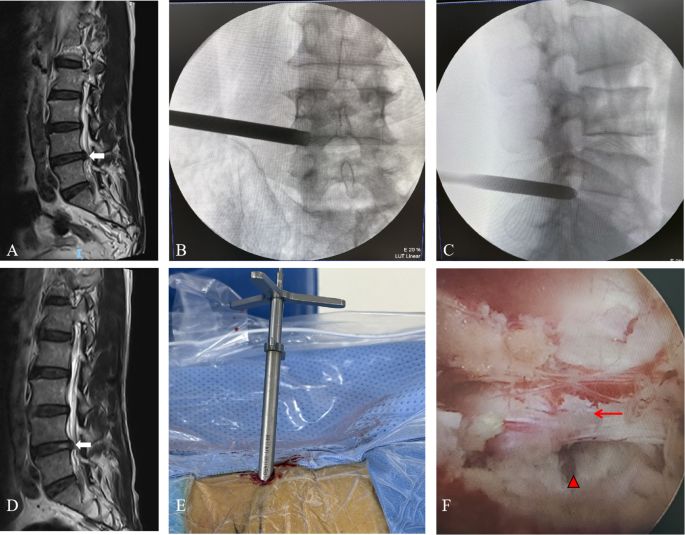

Patients were placed in the prone position. Premedication included intravenous midazolam (1–2 mg), with dosing adjusted for renal and hepatic function. Intraoperative sedation with a propofol infusion (10–30 µg/kg/min) was administered in 18.8% (12/64) of patients to alleviate discomfort, with no episodes of respiratory depression. For local anesthesia, 1% lidocaine was administered via layered infiltration (skin and subcutaneous tissue: 10 mL; facet joint capsule: 5 mL; perineural region of the nerve root in the foramen: 3 mL (total dose ≤ 200 mg)). Intraoperative patient movement or discomfort requiring additional local anesthetic occurred in 9.4% (6/64) of cases, and no patient required conversion to general anesthesia. The target level was identified using C-arm X-ray fluoroscopy. The puncture point was located 12–15 cm from the midline, with the needle angled at 15–25° to the horizontal plane. Fluoroscopy was used to confirm the position of the needle tip adjacent to the medial pedicle wall in the anteroposterior view and superior to the posterior disc margin in the lateral view. A 10 mm skin incision was made. Access was dilated using sequential dilators. Foraminoplasty, potentially involving partial facetectomy, was performed using a reamer if necessary. A working cannula was inserted, and the endoscope was installed. Under endoscopic visualization, the herniated disc fragment was identified and removed using pituitary forceps. The endoscope was maneuvered to explore and release the nerve root. After adequate decompression and absence of active bleeding were confirmed, the endoscope and working cannula were removed. The incision was then closed with a simple interrupted suture. A sterile dressing was applied to complete the procedure (Fig. 1).

Percutaneous endoscopic transforaminal discectomy (PETD) was performed on an 88-year-old male patient with L4-L5 disc herniation. (A) Preoperative magnetic resonance image indicating L4-L5 disc herniation (arrow). (B) Intraoperative anteroposterior radiograph demonstrating the position of the working cannula. (C) Intraoperative lateral radiograph confirming the placement of the working cannula at the posterosuperior margin of the vertebral body. (D) Postoperative magnetic resonance image revealing a substantial reduction of the L4-L5 disc herniation (arrow). (E) Operative working cannula placed. (F) Intraoperative endoscopic view illustrating the nerve root (arrow)and intervertebral space (triangle).